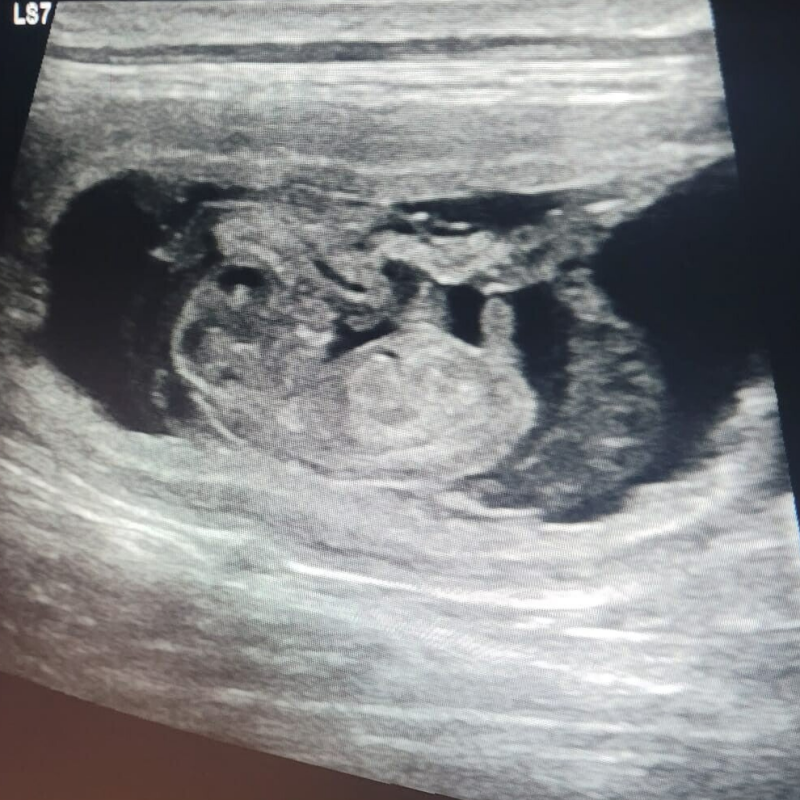

Maar goed nieuws! Cato is drachtig! Ze heeft het zo goed gedaan en wat is ze toch ontzettend lief, de dierenartsen zeiden het vandaag opnieuw. Daar zijn wij het natuurlijk helemaal mee eens!